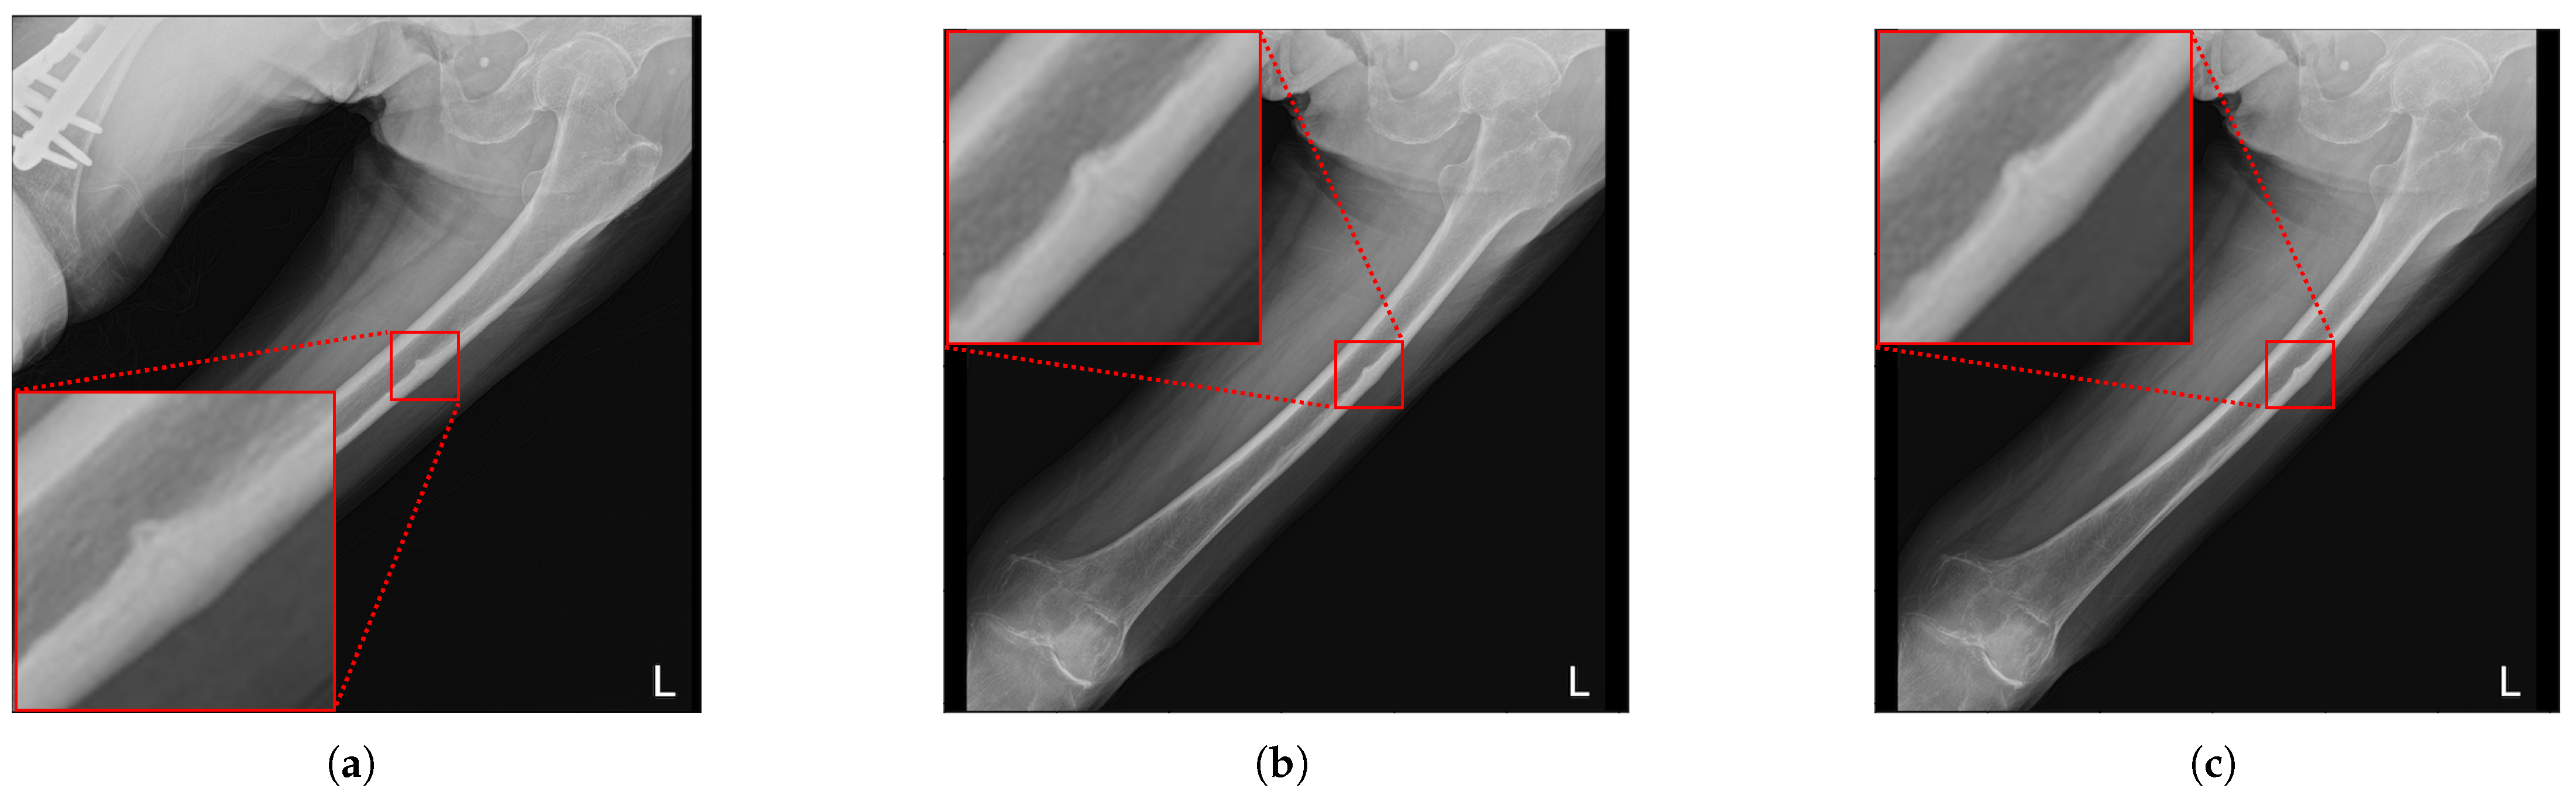

5.1. Analysis of Data Changes After Preprocessing